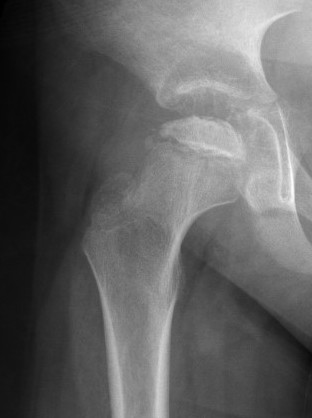

Xray

- may be normal

- small, sclerotic epiphysis

- joint space widening

- increased density of ossific nucleus & cessation of growth

XRay - Fragmentation of Physis